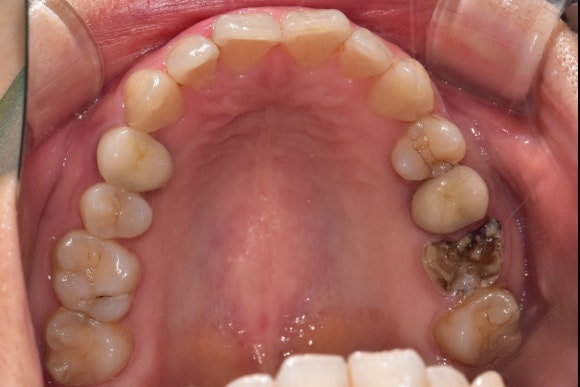

처참하게 부러진 치아입니다.

크라운째로 빠져서 오셨던 것 같습니다.

젊은 여자분이셨는데...

웃으면 보이는 보이는 위치에 치아가 없어져서 매우 당혹스러워하셨습니다.

난생처음 임플란트를 해야 한다는 두려움과 함께요.